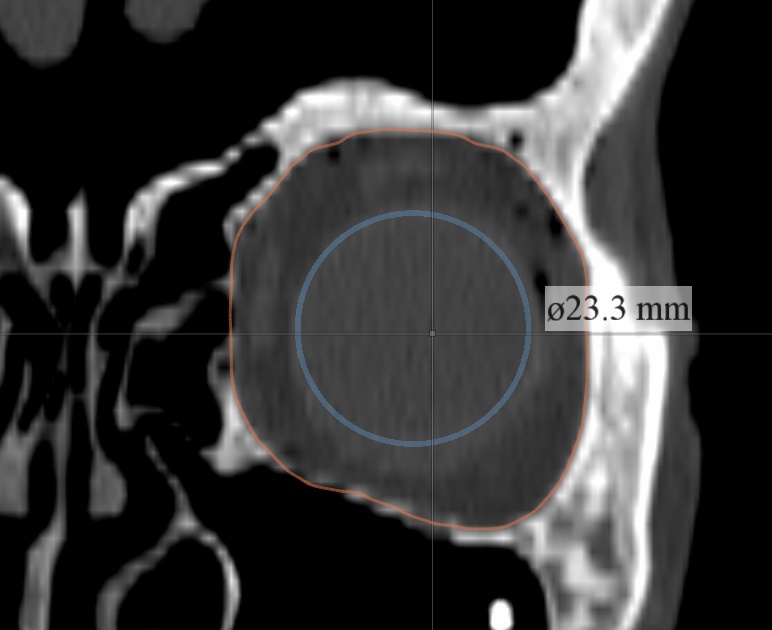

Stratovan Maxillo™ computes orbit (eye socket) volumes and bony contour shapes directly from x-ray computed tomography (CT) image data. Maxillo is intended for research use only by otolaryngologists, ENTs, plastic, and maxillofacial researchers investigating orbit morphology, shape, volume, and globe position. Maxillo utilizes a patent-pending image segmentation method.